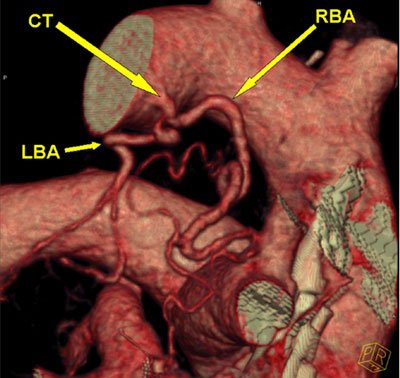

Procedure in which the blood supply of abnormal and diseased part of lung is blocked with medicine. A small puncture is made in blood vessel of thigh region with needle through which wire passed and sheath placed. Angiography done with catheter under X-ray guidance.